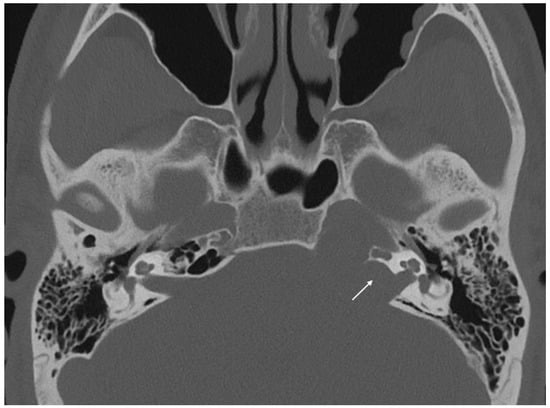

Imaging data from each patient were examined by an expert radiologist and an ENT specialist focusing attention not only on the location of the cyst, but also on the adjacent structures involved. Considering the available literature on symptoms and hypothesized regions of radiological involvement, we established a reproduceable pre-operative radiologic map to better correlate typical symptoms, such as headache, hearing loss, vestibular symptoms, tinnitus, otitis media, diplopia, and facial paresthesia, with PACG. The following regions were considered: (1) temporal lobe/posterior fossa compression (Figure 1); (2) Meckel’s cave compression (Figure 1); (3) Eustachian tube compression/erosion (Figure 2); (4) internal auditory canal erosion (Figure 3); (5) cochlear basal turn erosion (Figure 4); (6) Dorello canal involvement (Figure 5); (7) jugular tubercle erosion. The latter parameter was introduced to evaluate its possible correlation with an atypical clinical presentation, namely fainting. To standardize all these radiological examinations, the jugular tubercle was defined in axial sections as the bony convexity medial to the jugular foramen just above the hypoglossal canal; in coronal sections, it is the bony part directly above the hypoglossal canal (Figure 6).

Figure 4. Axial CT scan showing erosion of the right cochlear basal turn (white arrow) by a cholesterol granuloma.